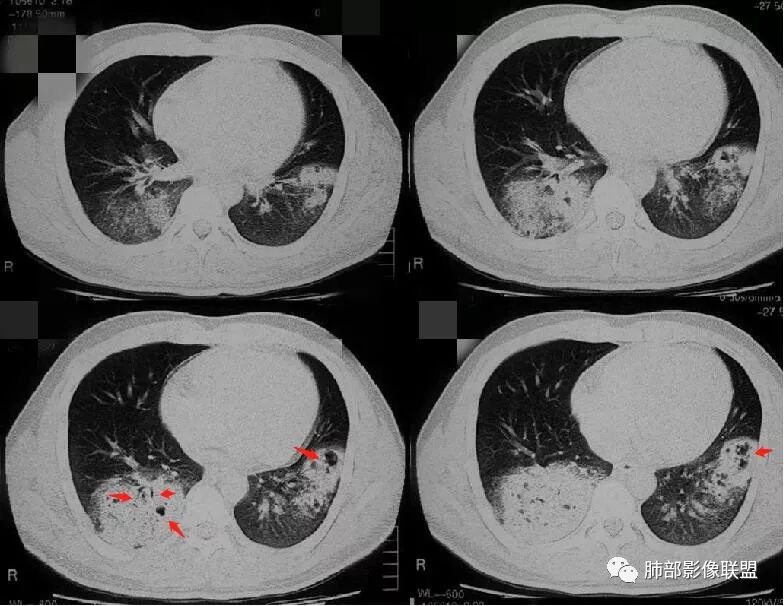

病灶的形态与分布如何?

右肺中叶及下叶大片实变影及双肺多发腺泡结节,局部成簇的腺泡结节融合成片,以外围及胸膜下分布为主

病灶的走行情况如何?

磨玻璃结节沿支气管飘散并落脚其他肺叶和肺段

病灶边缘情况如何?

以膨隆为主,局部稍平直、收缩

病灶内支气管情况如何?

支气管走形僵直、狭窄、中断,分支减少,呈“枯树枝”改变(图1-4红色短箭头)。可惜没有增强,不能了解病灶强化及血管情况。

病灶内的坏死情况?

有少许小空泡,未见明显液化坏死

周围肺野情况如何?

周围肺野有边界清楚GGO,局部中轴间质明显增厚并呈结节样改变(图1绿色箭头),树芽征不明显

老年男性,有发热、咳嗽、咳少量浓痰,呼吸困难,临床病程不详,但是影像上有实变、簇状分布的腺泡结节及枯树枝征,老年男性,高度怀疑肺炎型肺癌;肺炎型肺癌的病理基础是癌细胞沿肺泡壁、小叶中心、腺泡腔成簇、匍匐性生长,并沿肺泡孔及支气管播散,并且癌细胞分泌粘液引起肺组织实变,液化坏死少见,而干酪性肺结核多有虫噬样空洞及液化坏死区,结核支气管多为壁增厚 、扩张,肺癌的支气管多为狭窄堵塞、粗细不均。

温馨提示:病例2病理结果细支气管肺泡癌此定义取消,现归为腺癌,也是肺炎性肺腺癌的主要类型之一。详细内容请参考肺部影像联盟文章“不同时期腺癌的病理影像诊断”。